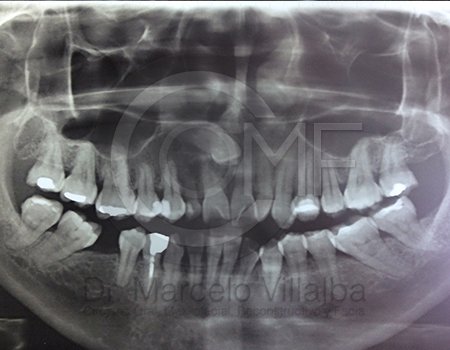

Antes de la extracción se realiza una valoración clínica y estudios de imagen, como radiografías panorámicas o tomografías, para conocer la posición del tercer molar, su relación con los nervios y planificar un procedimiento seguro y adecuado para cada paciente.

No es recomendable. Antes de extraer terceros molares es necesario realizar una valoración clínica y estudios de imagen para conocer la posición del diente, su relación con los nervios y el tipo de procedimiento más seguro para cada paciente.

Algunas extracciones simples de otras piezas dentales pueden ser realizadas por un odontólogo general; sin embargo, por la complejidad que presentan los terceros molares, o si se encuentran retenidos, impactados o cerca de estructuras importantes, se recomienda que el procedimiento sea realizado por un cirujano maxilofacial para mayor seguridad y control del tratamiento.